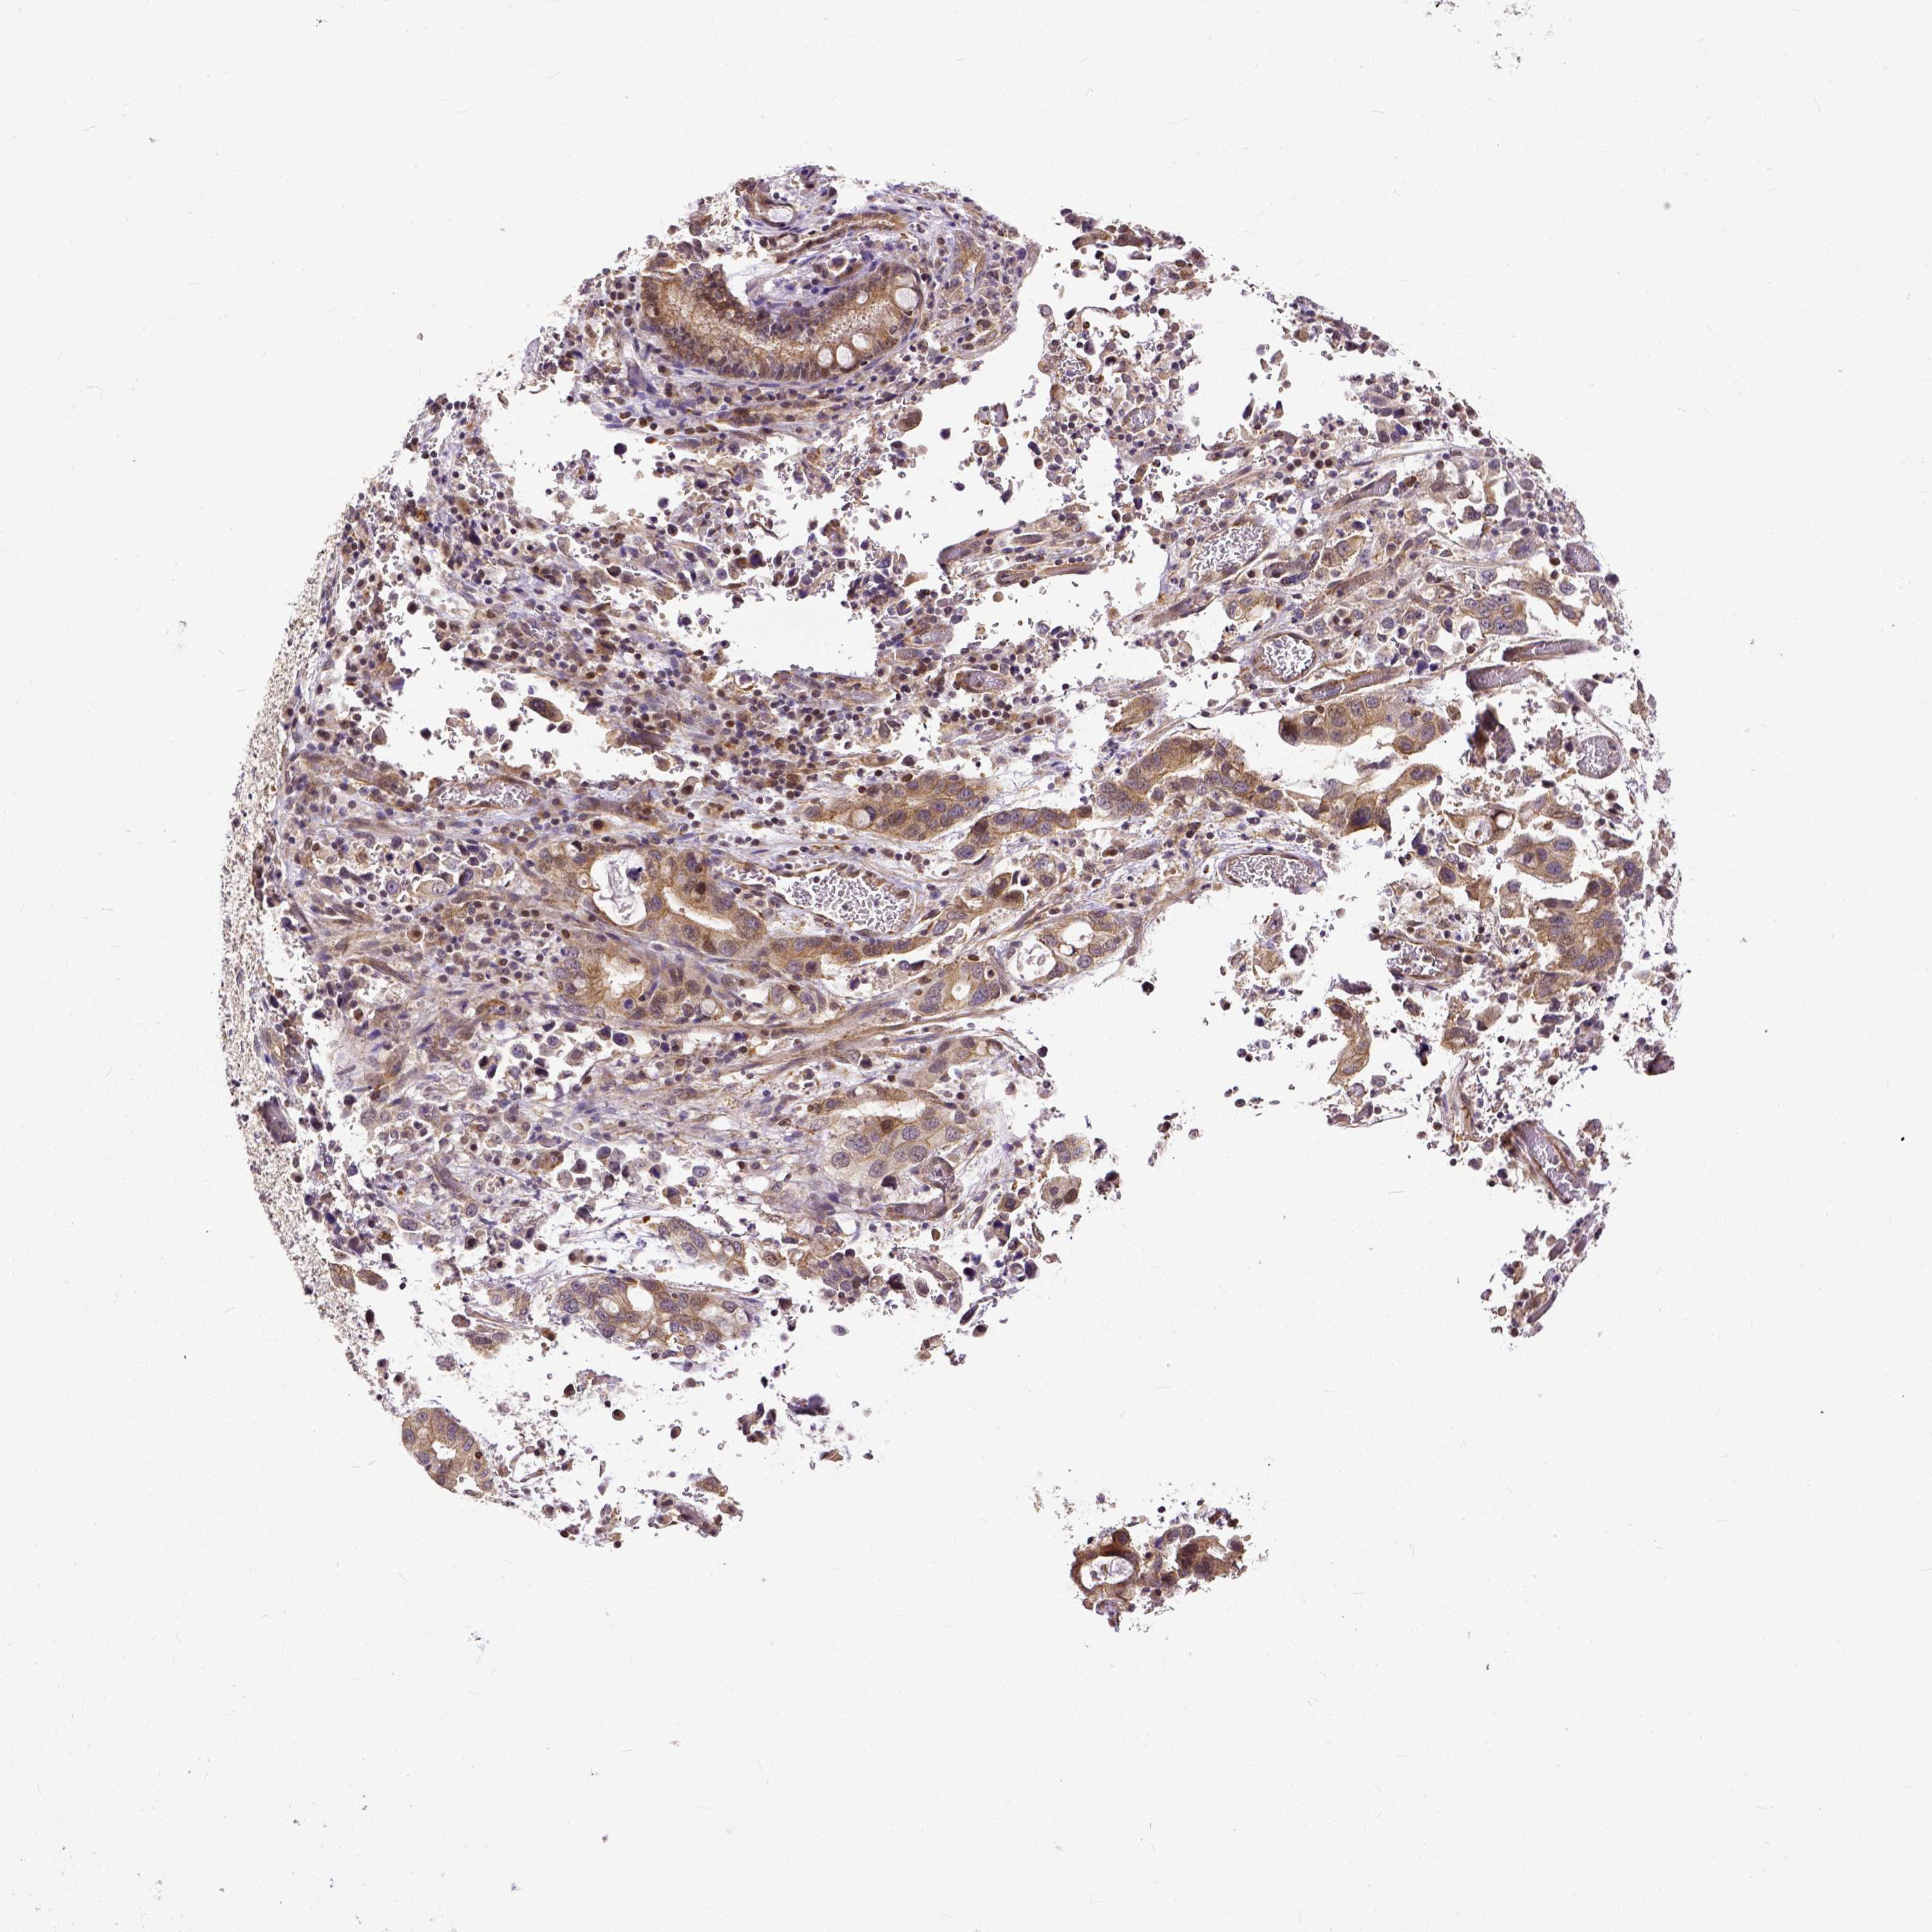

STOMACH CANCER - Protein expressioni

A mouse-over function shows sample information and annotation data. Click on an image to view it in a full screen mode. Samples can be filtered based on level of antibody staining by selecting one or several of the following categories: high, medium, low and not detected. The assay and annotation is described here.

Note that samples used for immunohistochemistry by the Human Protein Atlas do not correspond to samples in the TCGA dataset.

Antibody stainingi

Antibody staining in the annotated cell types in the current human tissue is reported as not detected, low, medium, or high, based on conventional immunohistochemistry profiling in selected tissues. This score is based on the combination of the staining intensity and fraction of stained cells.

Each image is clickable and will lead to virtual microscopy that enables deeper exploration of all samples and also displays staining intensity scores, fraction scores and subcellular localization as well as patient and tissue information for each sample.

Antibody HPA000694

Antibody CAB068185

Staining

High

Medium

Low

Not detected

Intensity

Strong

Moderate

Weak

Negative

Quantity

>75%

75%-25%

<25%

None

Location

Nuclear

Cytoplasmic/membranous

Cytoplasmic/membranous,nuclear

Adenocarcinoma, NOS